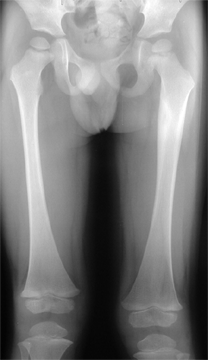

La croissance des membres inférieurs se fait

de la façon suivante :

c’est à dire environ 35 cm : 20 cm pour le fémur 15 cm pour le tibia |

La croissance du fémur

est forte pendant les 5 premières années de vie : ainsi

à l’âge de 5 ans le fémur mesure 60 % de sa

taille finale. A partir de 5 ans la croissance fémorale se ralentit

à 2 cm/an et reste uniforme jusqu’à la puberté

En fin de croissance, la longueur du fémur

est de 45 cm : elle a été multipliée par 5.

La croissance du tibia

est inférieure à celle du fémur, même si

son profil de croissance est calqué sur celui du fémur :

forte croissance pendant les 5 premières années de vie,

puis net ralentissement à partir de 5 ans.

A cet âge, le tibia grandit de 1,75 cm/an.

En fin de croissance, la longueur du tibia est de

35 cm : elle a été pratiquement multipliée par

5.